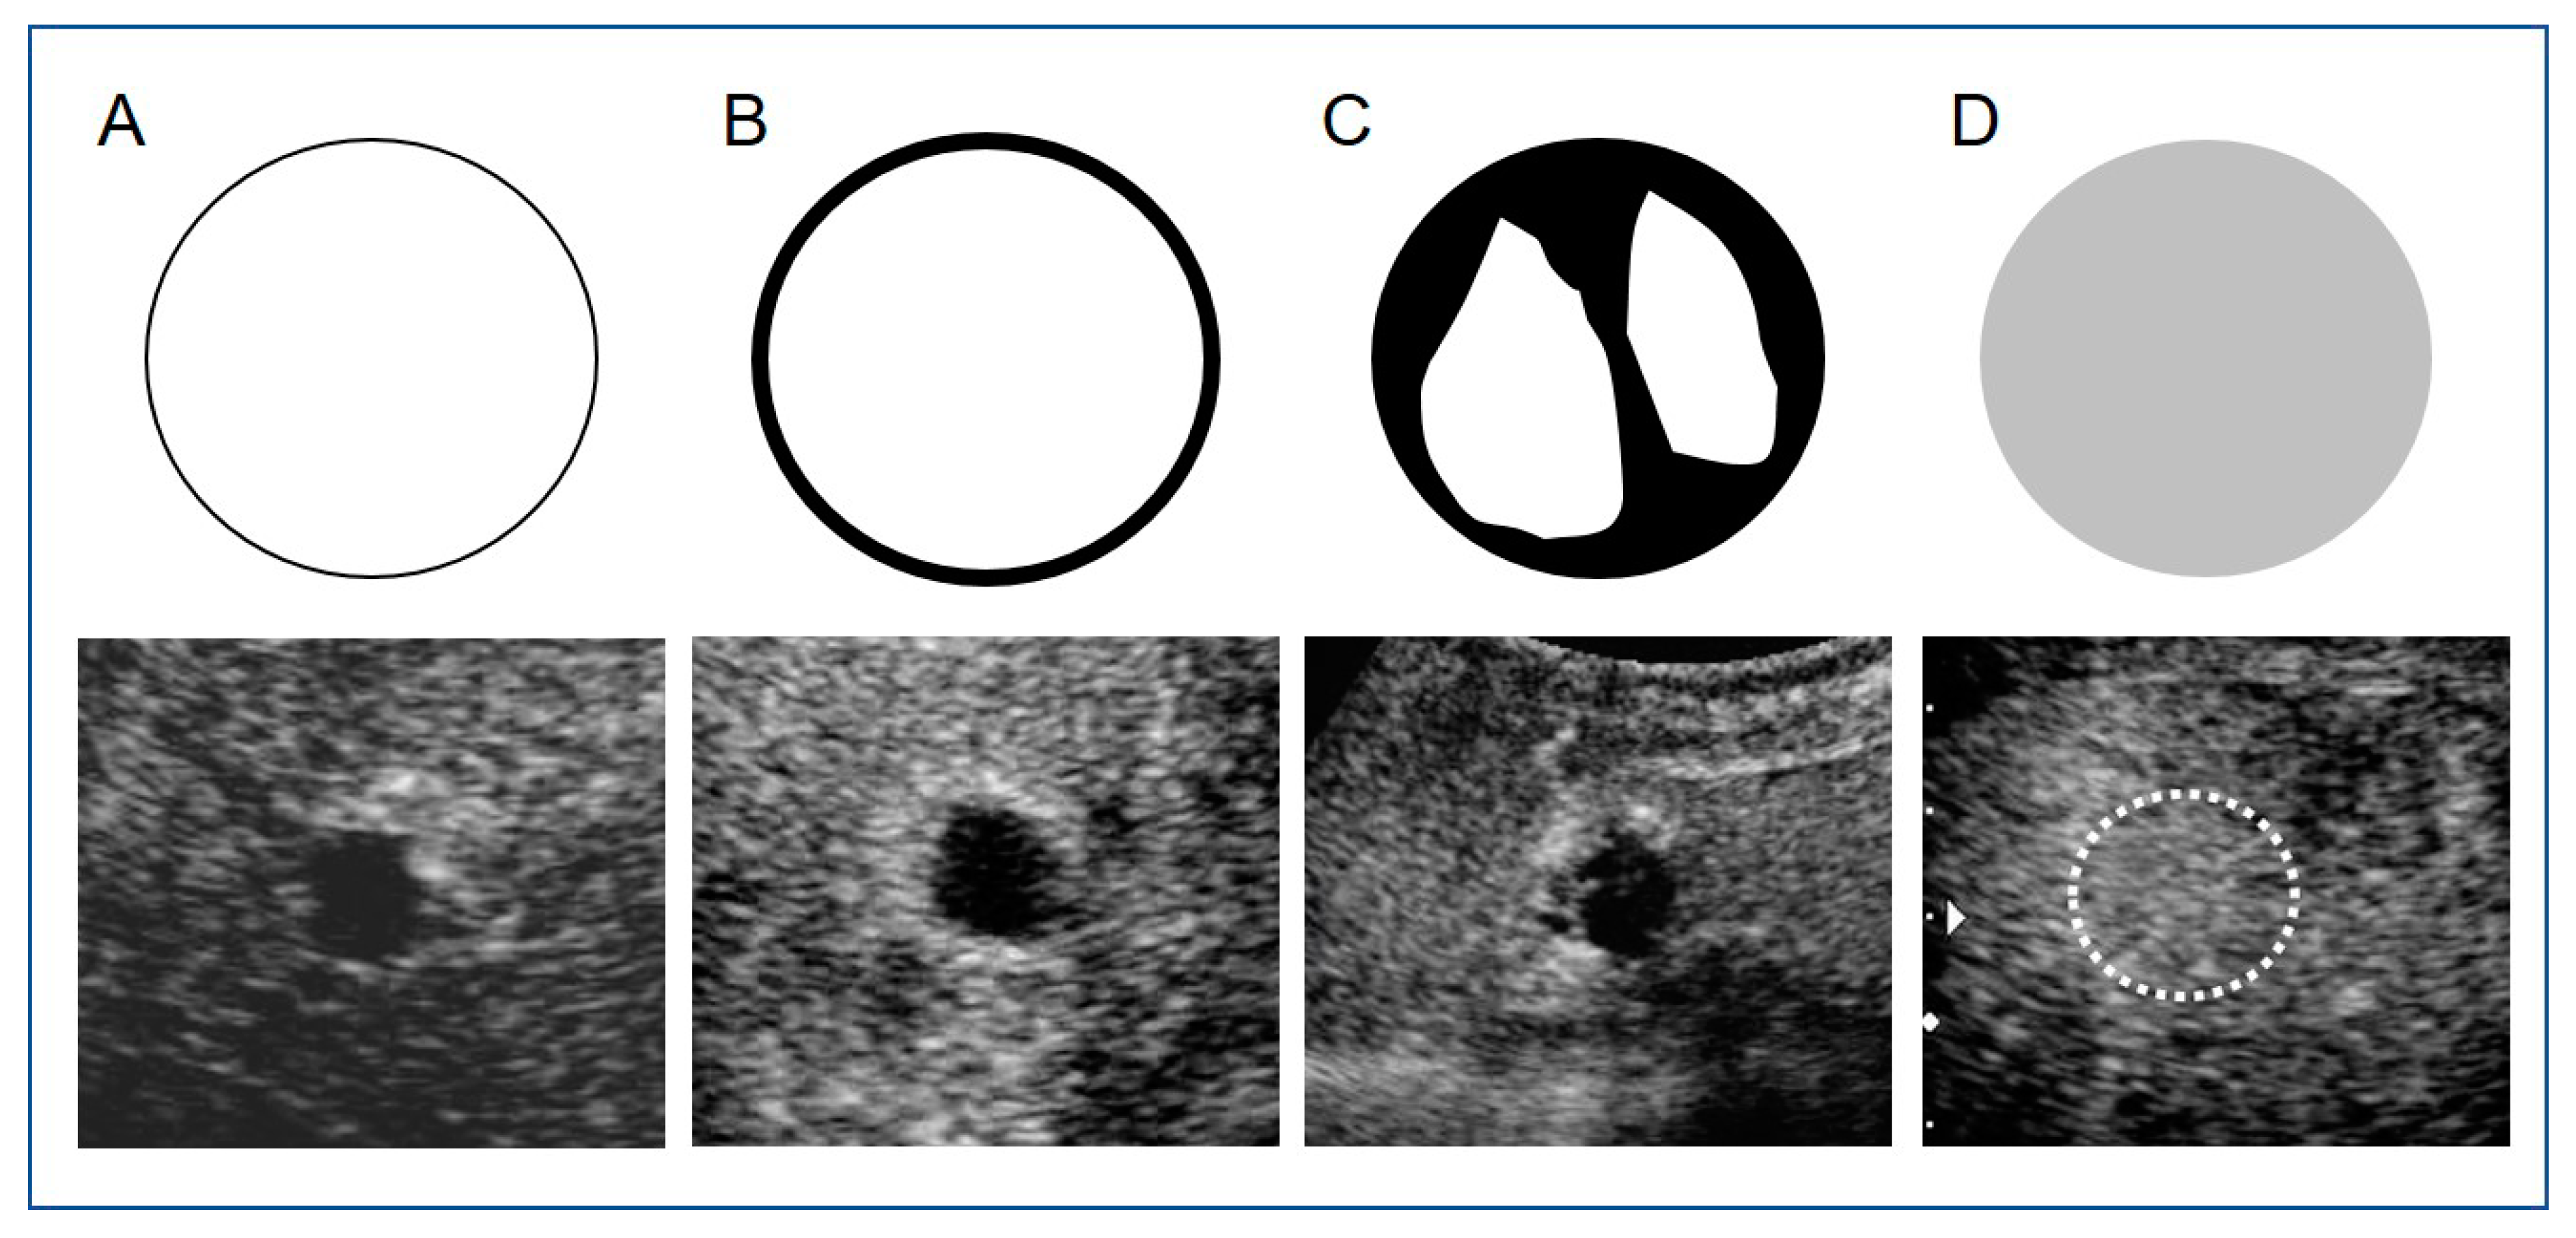

2.2. CEUS Imaging

2.5. Image Analysis